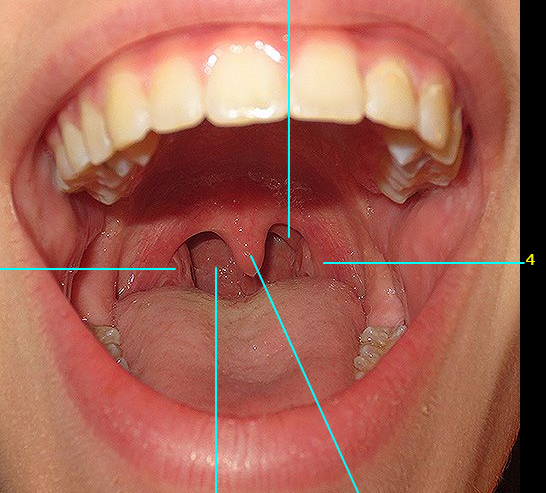

Name #4

Palatoglossal arch / fold (anterior fauces)

Name #2

Palatopharyngeal fold (posterior fauces)